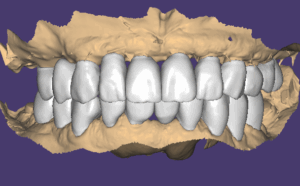

모든 임플란트는 골융합이 잘 되었고 스캔바디를 끼우고 스캔을 한 다음 디자인해서 치아를 만들었습니다. 저희 병원은 치기공 100% 모두 자체적으로 가공을 하고 있어요. 모든 장비를 다 갖추고 있구요. 기공을 제가 직접 하게 된 스토리는 길어서 다른 글에서 보시면 될 거 같아요. 아무래도 제가 임상에서 깨달은 부분을 디자인에 직접 적용하기 위함이 큽니다.

이렇게 해서 전체적이 치료가 예쁘게 튼튼하게 잘 마무리가 되었습니다. 전체임플란트 치료를 수십년간 수천명을 치료하면서 점점 치료가 발전하고 있어요. 지금의 치료법까지 오는 길이 쉽지는 않았지만 그 길을 찾아오는 여정이 흥미롭고 행복했습니다.

이 분은 잇몸질환으로 치아를 뽑지 않았기 때문에 비교적 뼈의 모양이 잘 유지되어 있어서 결과가 더 예쁜 것 같아요.